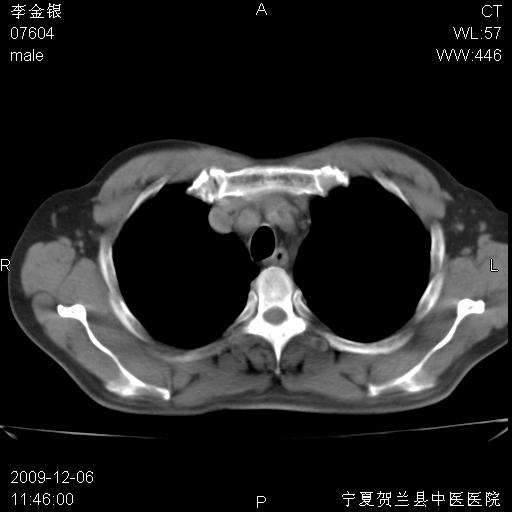

该病人 ,男,62岁,主因咳痰带血两天

考虑右肺中央型占位性病变并阻塞性肺炎.(右肺上叶支气管变窄),建议支纤镜检查.

支气管壁明显增厚 管腔狭窄,腔静脉后多个淋巴肿大,结合年龄病史考虑右肺上叶中央型肺癌并阻塞性肺炎